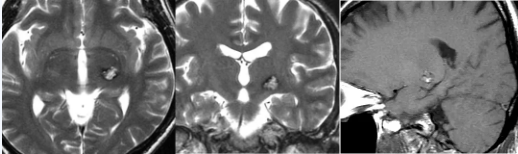

近期远程视频中还有一名41岁脑干血管畸形伴出血患者宋女士,左侧丘脑后方血管畸形破裂出血、被送进ICU,先后进行MRI和DSA等检查为明确诊断。从MRI影像能否确诊为海绵状血管瘤?有可能是其他血管畸形吗?处理方式又有何不同?

巴教授评估回复

“这个在核磁共振成像中也能看到,从病灶的性质来说,我们把海绵状血管畸形与静脉畸形、动静脉畸形(AVM)和毛细血管扩张区分,这几种情况没有明确的界限。我们把它们分开来讨论,是因为它们的预后和表现不同。从性质上来说这种明确的划分并不是关键的,有时我们会遇到一种所谓的混合病变,甚至可能是一个非常小的动静脉畸形与海绵状血管瘤的结合,我们称之为混合病变。在本病例中也很有可能是这种情况。

重要的是这个病变造成了什么,它已经引起了出血,所以不管它是什么类型,我们的治疗目的是避免以后的出血,这是手术的指征。不管它是什么,都不要紧,我们所希望的是病人将来不会有(再)出血的风险。因此,切除血管畸形非常重要,否则以后可能会再次出血。”